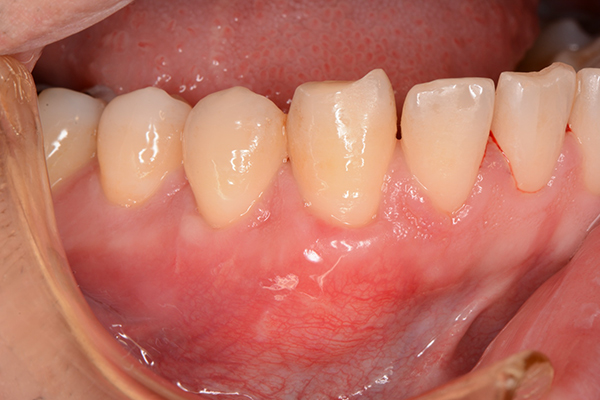

歯周病による歯茎や口腔組織の損傷を修復し、歯周病の進行を防ぐための治療法です。歯周病によって歯茎が退縮し、歯根が露出してしまった場合、結合組織移植術は歯根を覆うための組織を提供し、美的および機能的な改善を図ります。

- FGG/遊離歯肉移植術

-

遊離歯肉移植とは患者様の口腔内から取られた「遊離歯肉」と呼ばれる歯茎組織を、歯肉の欠損部分に移植することで、歯茎の再建や歯周病の治療を行います。

※血が出ている画像もあるので閲覧にご注意ください